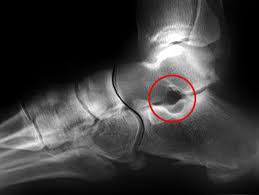

הסינוס הטרסלי הינו מרווח אנטומי הנוצר בין עצם הטלוס ובין הקלקנאוס, פיתחו בפן הלטראלי של הפרק מעט אינפריורית לרצועה ה-anterior talo fibular ligament, גובל משני צידיו בפסטים הקלקנאליים, ונמשך לאחור בתעלה הטרסלית הצרה.הסינוס הטרסאלי מכיל: ליגמנט הסרוויקאלי- cervical ligament

בדיקות רלוונטיות לאיתור סינדרום הסינוס הטארסלי בכף הרגל

mri הינה הבדיקה הרלוונטית ביותר להערכת מצב הסינוס הטרסאלי.הזרקת אנסטזיה מקומית, במידה וישנה ירידה משמעותית

ברמת הסימפטומיםסימן לסינדרום התעלה הטרסאלית חיובי.